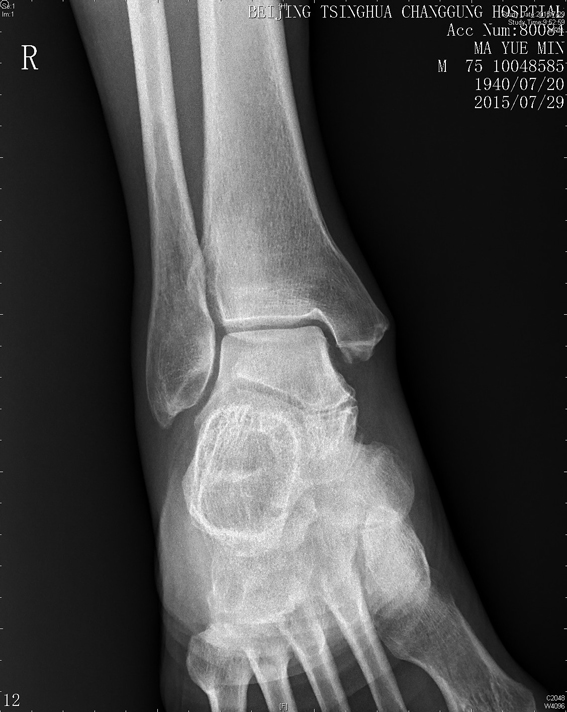

右踝关节X线示:踝关节退行性变。